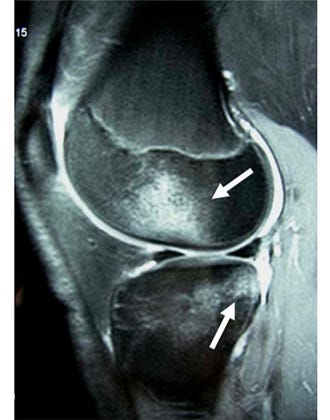

Bone bruises after an ACL injury deserve more respect than they sometimes get.

Not all ACL injuries follow the same rehab trajectory, and bone bruising is one big reason why. A larger bone bruise often reflects a bigger joint insult, which can mean more pain, more irritability, and a slower early recovery.

That matters, because two people can both have an “ACL injury” on paper, but present very differently in the clinic.

Big takeaway: same diagnosis doesn’t always mean same timeline. The bigger the bone bruise, the more likely rehab may need a little more patience, a little more symptom-guided progression, and a little less rushing.

Image Reference: Nakamae et al (2006)